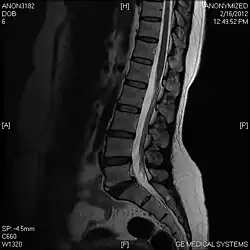

Limbus vertebra

A limbus vertebra is a bone tubercle formed by bone trauma on a vertebral body, bearing a radiographic similarity to a vertebral fracture. The anterior-superior corner of a single vertebra is the common site for this defect although it can also be seen at the inferior corner as well as the posterior or anterior margin. Anatomically, it is assumed to be an intra-vertebral body herniation of the disc material occurring during adolescent growth spurt when the ring apophysis has not yet fused. It was first described by Schmorl in 1927[1] and later in detail by Leif Sward and Adad Baranto.

Viewed in a lateral radiograph, it appears as a triangular shaped bone fragment, not unlike an anterior lip fracture, but with softer edges.

Limbus vertebra is not always symptomatic, but severe cases may lead to more serious pathological conditions and chronic pain. In rare instances, a posterior limbus vertebra has been described causing radiculopathy due to nerve root compression.[2]